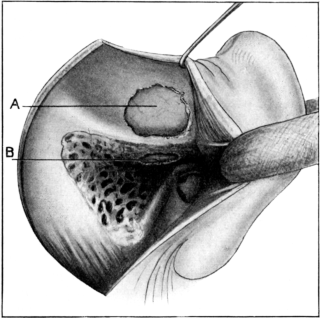

| 185. | Polypus arising from the Attic Region | 332 |

| 186. | Anatomical Preparation of the Middle Ear | 335 |